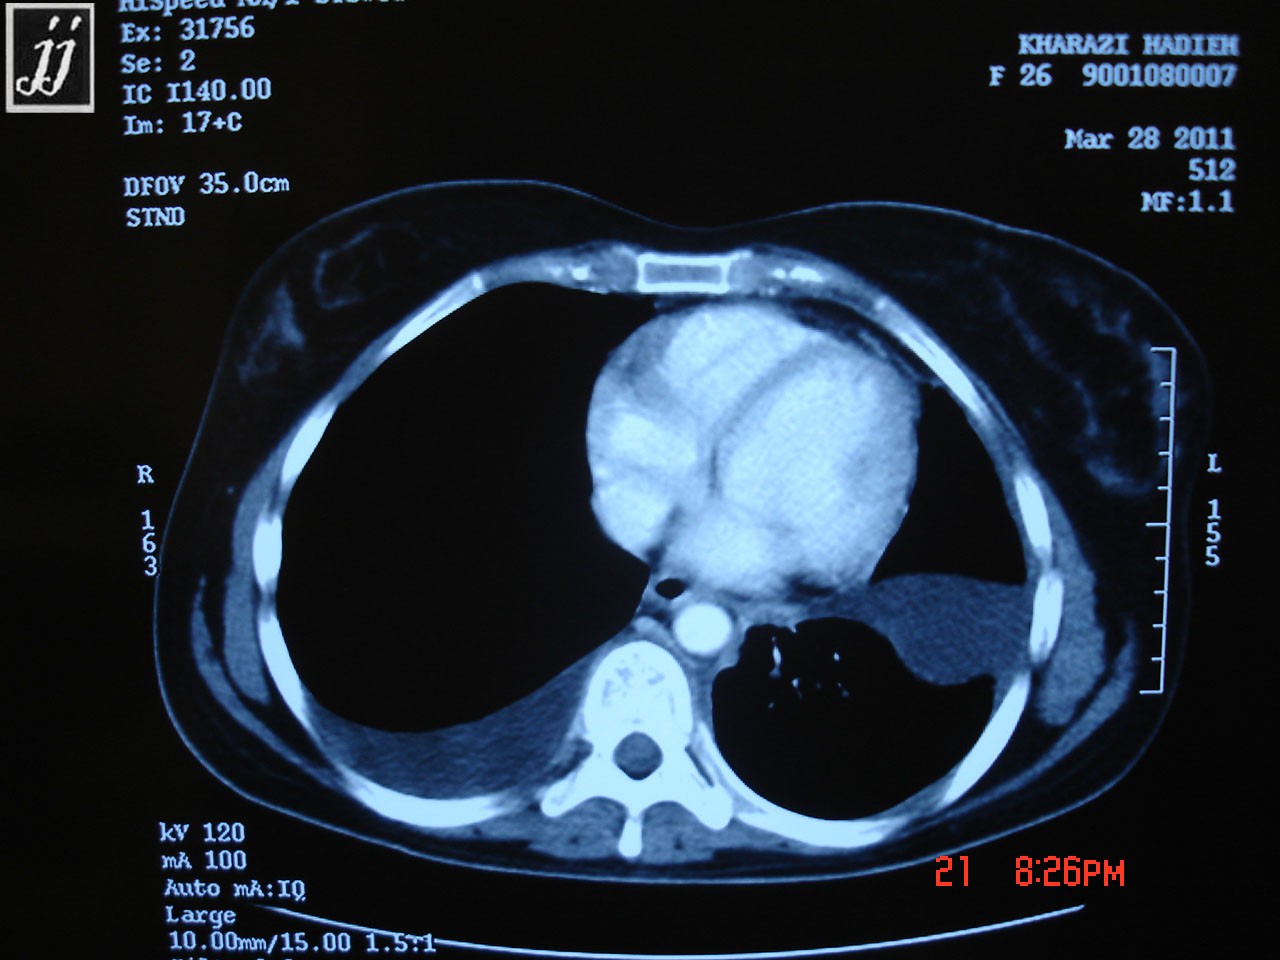

Equine Kidney Disease A biopsy of the kidneys. the most common clinical signs of ckd are weight loss, polyuria/polydipsia, and ventral edema. Increased water intake (“average” intake is 5 to 7 gallons of water/day) increased urination. in horses, ckd is uncommonly reported in the literature and has until now received little scientific attention despite being regularly encountered in. A variety of laboratory tests. Creatinine only allows detection of kidney disease when 60 to 75% of the glomerular function is lost and is. horses don’t typically engage in behaviors that batter each other’s kidneys; However, there are many causes of both. signs of kidney disease in horses. Glomerular filtration rate is the. feeding horses with chronic kidney disease to maintain body condition and quality of life is vital. The aim of this consensus statement is to summarize and appraise scientific evidence. here’s what you need to know about kidney disease and failure, including how to spot signs that your horse has problems with. luckily, renal complications due to nsaids are well described with the result that there is judicious use of these medications in. the aim of this consensus statement is to summarize and appraise scientific evidence and combine this with the clinical. chronic kidney disease in horses is a rare diagnosis, with one study finding a prevalence of 0.12% in a hospitalised population, increasing to.